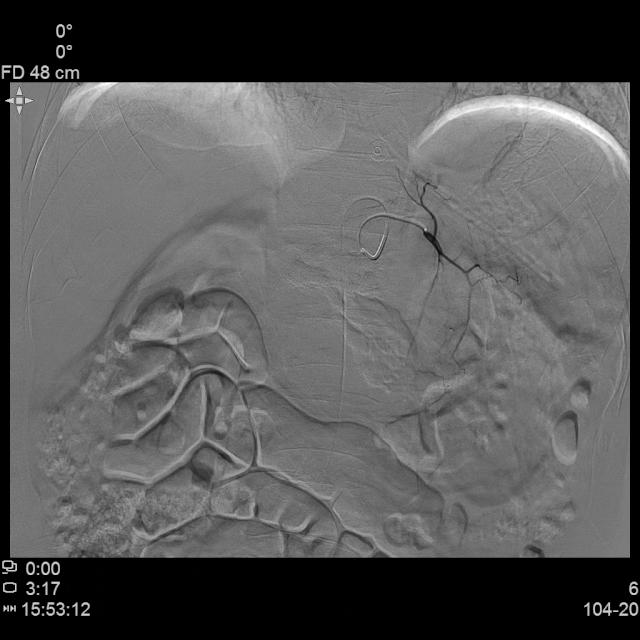

DSA造影显示胃左动脉分支肿瘤染色丰富

DSA造影显示胃网膜动脉分支肿瘤染色丰富